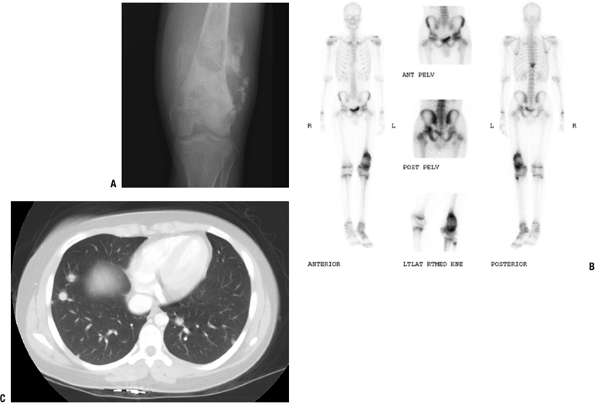

Most common site of metastasis: lungs (Fig. 6.1-4)

Figure 6.1-4 A 16-year-old boy with distal femoral lesion. (A) Plain radiograph shows abundant bone production and soft tissue extension strongly suggestive of an osteosarcoma. (B) Whole-body Tc-99 bone scan reveals a lesion of the ipsilateral acetabulum and thoracic spine. (C) CT axial image of the chest also reveals multiple pulmonary metastases.